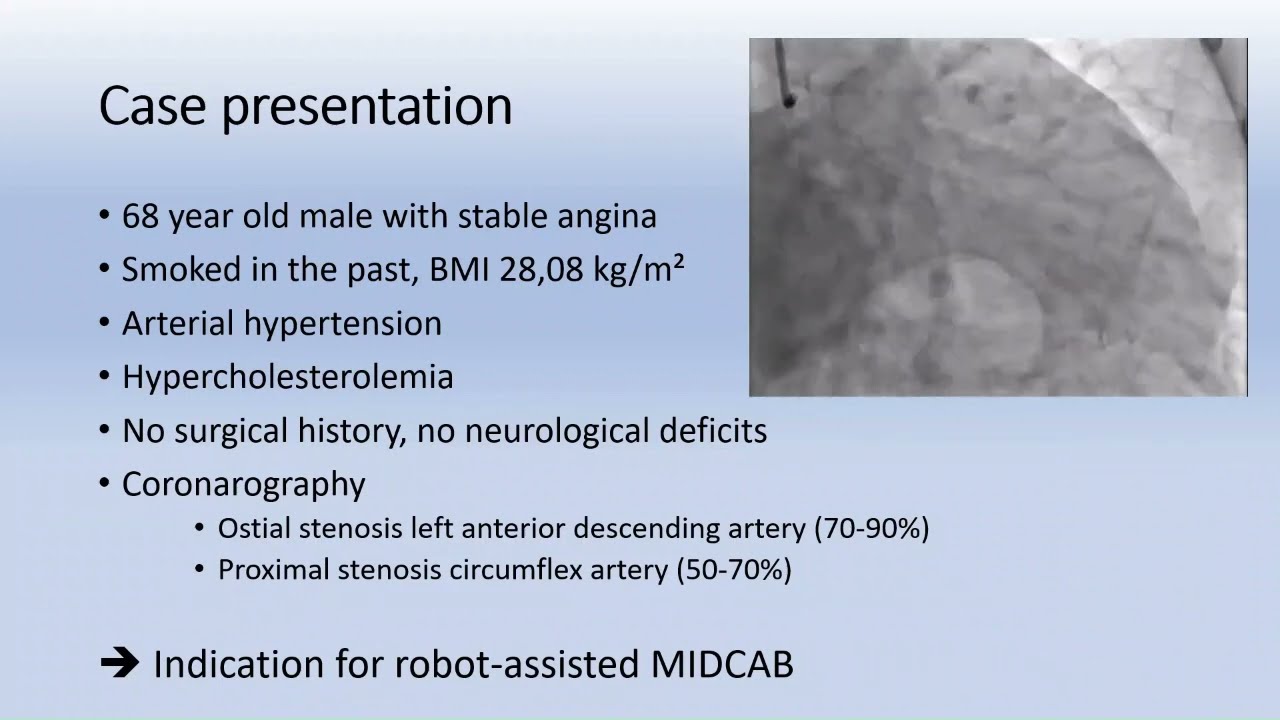

#219 Robot-assisted minimal invasive CABG using bilateral thoracic arteries- Dr. Michiel Algoet

KS Awards, Robotics, Surgeon ';